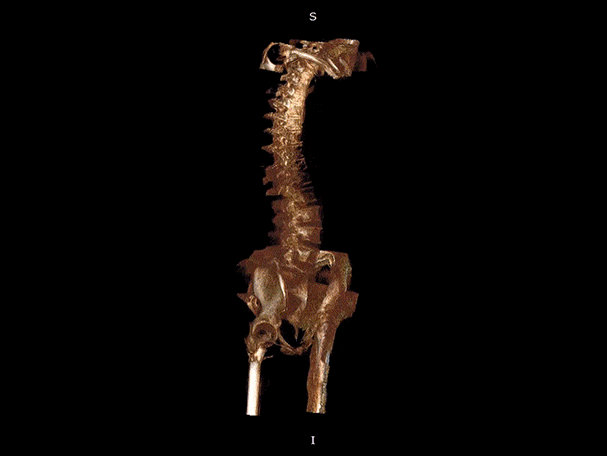

VR體繪制重建